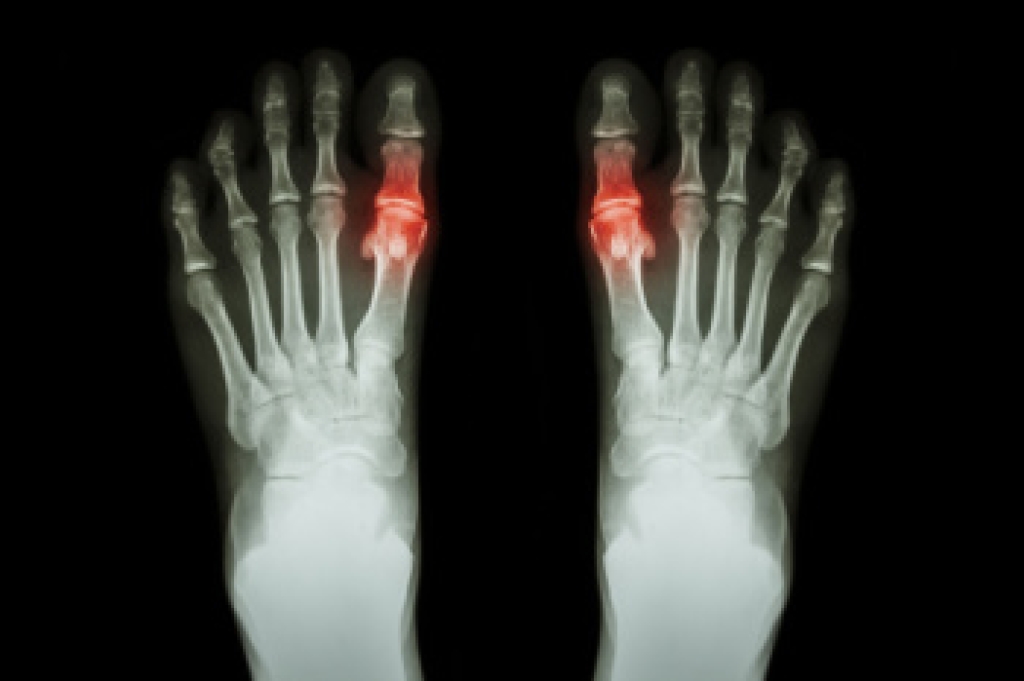

Chronic tophaceous gout is an advanced form of gout that develops when uric acid builds up in the body. The result is hard deposits, called tophi, that form around joints and soft tissues. Uric acid is a natural waste product, but high levels can lead to crystal formation that triggers inflammation, causing swelling, warmth, and severe pain. Over time, these deposits may grow and cause joint damage, stiffness, and reduced movement. They can also press on nearby nerves and affect walking. A podiatrist can diagnose chronic tophaceous gout through imaging or fluid testing, which identifies uric acid crystals. Treatment options include medication to lower uric acid levels and reduce inflammation, as well as care to protect the joints and prevent further damage. In severe cases, surgery may be needed to remove large tophi. If you are experiencing severe pain from gout, it is suggested that you make an appointment with a podiatrist for treatment.

Gout is a type of arthritis caused by a buildup of uric acid in the bloodstream. It often develops in the foot, especially the big toe area, although it can manifest in other parts of the body as well. Gout can make walking and standing very painful and is especially common in diabetics and the obese.

Gout can easily be identified by redness and inflammation of the big toe and the surrounding areas of the foot. Other symptoms include extreme fatigue, joint pain, and running high fevers. Sometimes corticosteroid drugs can be prescribed to treat gout, but the best way to combat this disease is to get more exercise and eat a better diet.